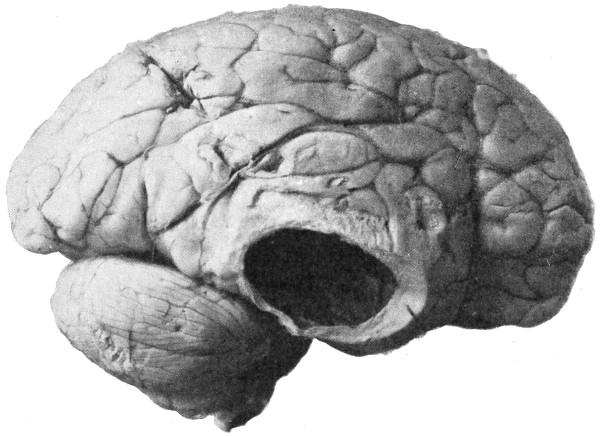

Fig. 20. An Occipital Cephalocele. (For further description, see text.)

1. Occipital cephaloceles—the commonest variety—occupy, anatomically, two positions (1) between the two lower segments of the occipital bone (inferior occipital cephaloceles), often involving the foramen magnum and sometimes complicated by a condition of cervical spina bifida, and (2) between the two upper segments of the occipital bone (superior occipital cephaloceles), occasionally involving the posterior fontanelle.

Sincipital cephaloceles are usually quite small, but the occipital variety and those situated in[35] the region of the anterior fontanelle frequently attain a great size (see Figs. 20-22).

Fig. 22. An Occipital Cephalocele. (For further description, see text.)

The child was 3 months old, and presented a tumour, the size of an orange, situated between the occipital protuberance and the nape of the neck. The mass was pedunculated, the stalk being about the size of a four-shilling piece in diameter. It was soft, translucent, irreducible, and swelled up on coughing. An attempt at removal was carried out, and, after incising the outermost layers, three ounces of cerebro-spinal fluid escaped. A second tumour was then found occupying the base of the swelling. This was also punctured, more fluid escaping. Both sacs were cut away and the wound sewn up. Death occurred on the third day, preceded by convulsions, retraction of the head and neck, and high fever. The autopsy showed that the fontanelles were widely open, the anterior measuring 4 inches from side to side and 212 from before backwards. The bones of the vault were markedly thinned. In the subdural space there was a quantity of fluid, and the cerebral substance was soft and diffluent, the convolutions flattened, and the ventricles distended. There was a broad gap in the occipital bone, extending downwards into the foramen magnum, and in this situation the cerebellum had bulged backwards into the protruding mass. (See Fig. 22).